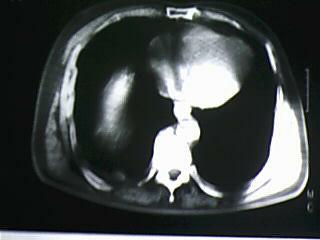

标题: CT19768:男 61岁 胸痛 咯血 一周。无发烧、无结核病史。 [打印本页]

标题: CT19768:男 61岁 胸痛 咯血 一周。无发烧、无结核病史。

纵隔窗图像不佳,怀疑右下叶支气管有狭窄,来几张清楚的,暂考虑----感染性病变----抗炎后复查

考虑 右下肺感染性病变,建议抗炎后复查。

考虑右肺下叶感染性病变;建议抗炎治疗后复查。